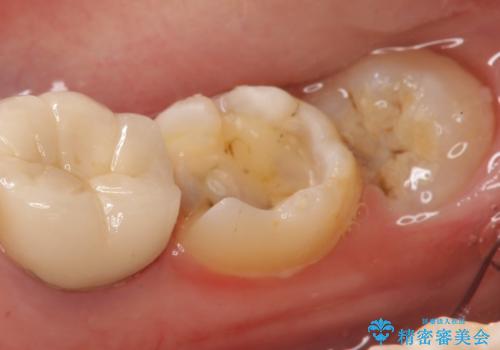

- 右下7の銀歯を白くしたいといらっしゃった方の症例です。

銀歯及び虫歯を除去後、セラミックインレーで修復を行いました。

当院のセラミックインレーはemaxという強度と審美性に優れた材料を使用しています。

またプレス方式でインレーを製作しているため、削り出しで製作するCADCAMより優れた適合性も持ち合わせており、虫歯が再発しにくい修復物です。